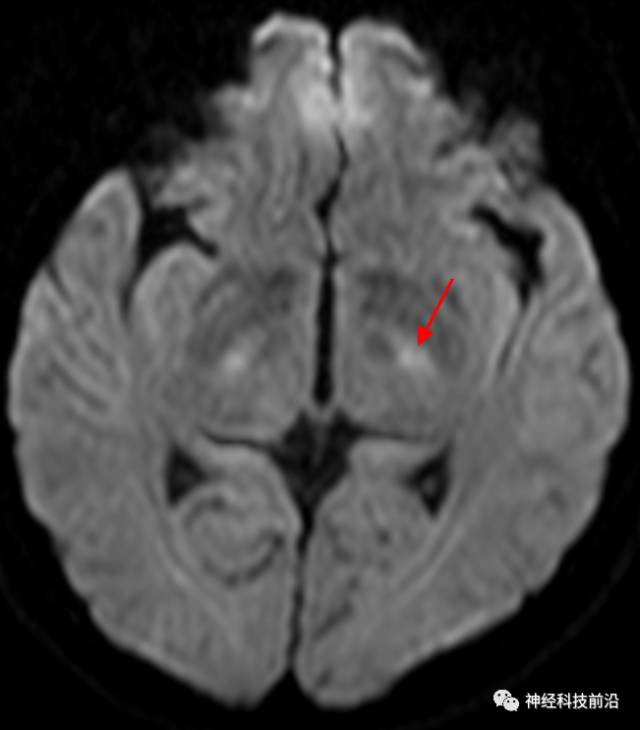

皮质脊髓束与皮质脑桥束的关系毗邻

终上所述:脑干高信号为一近环形纤维束,内囊后肢高信号为皮质脑桥束,皮质脊髓束在中脑位置略靠后。高信号位于中脑前缘,是皮质脑桥束的位置所在,另外有部分桥连纤维。